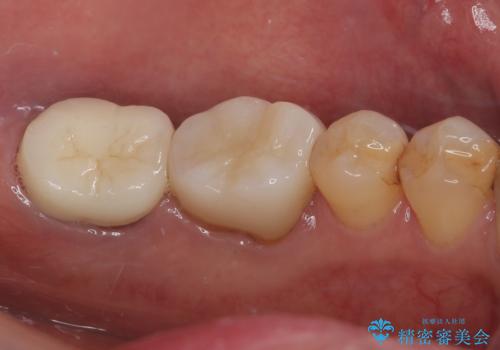

根管治療後は痛みもなくなりました。

強い咬合力による歯根破折を予防するためにナイトガードの使用も有効です。